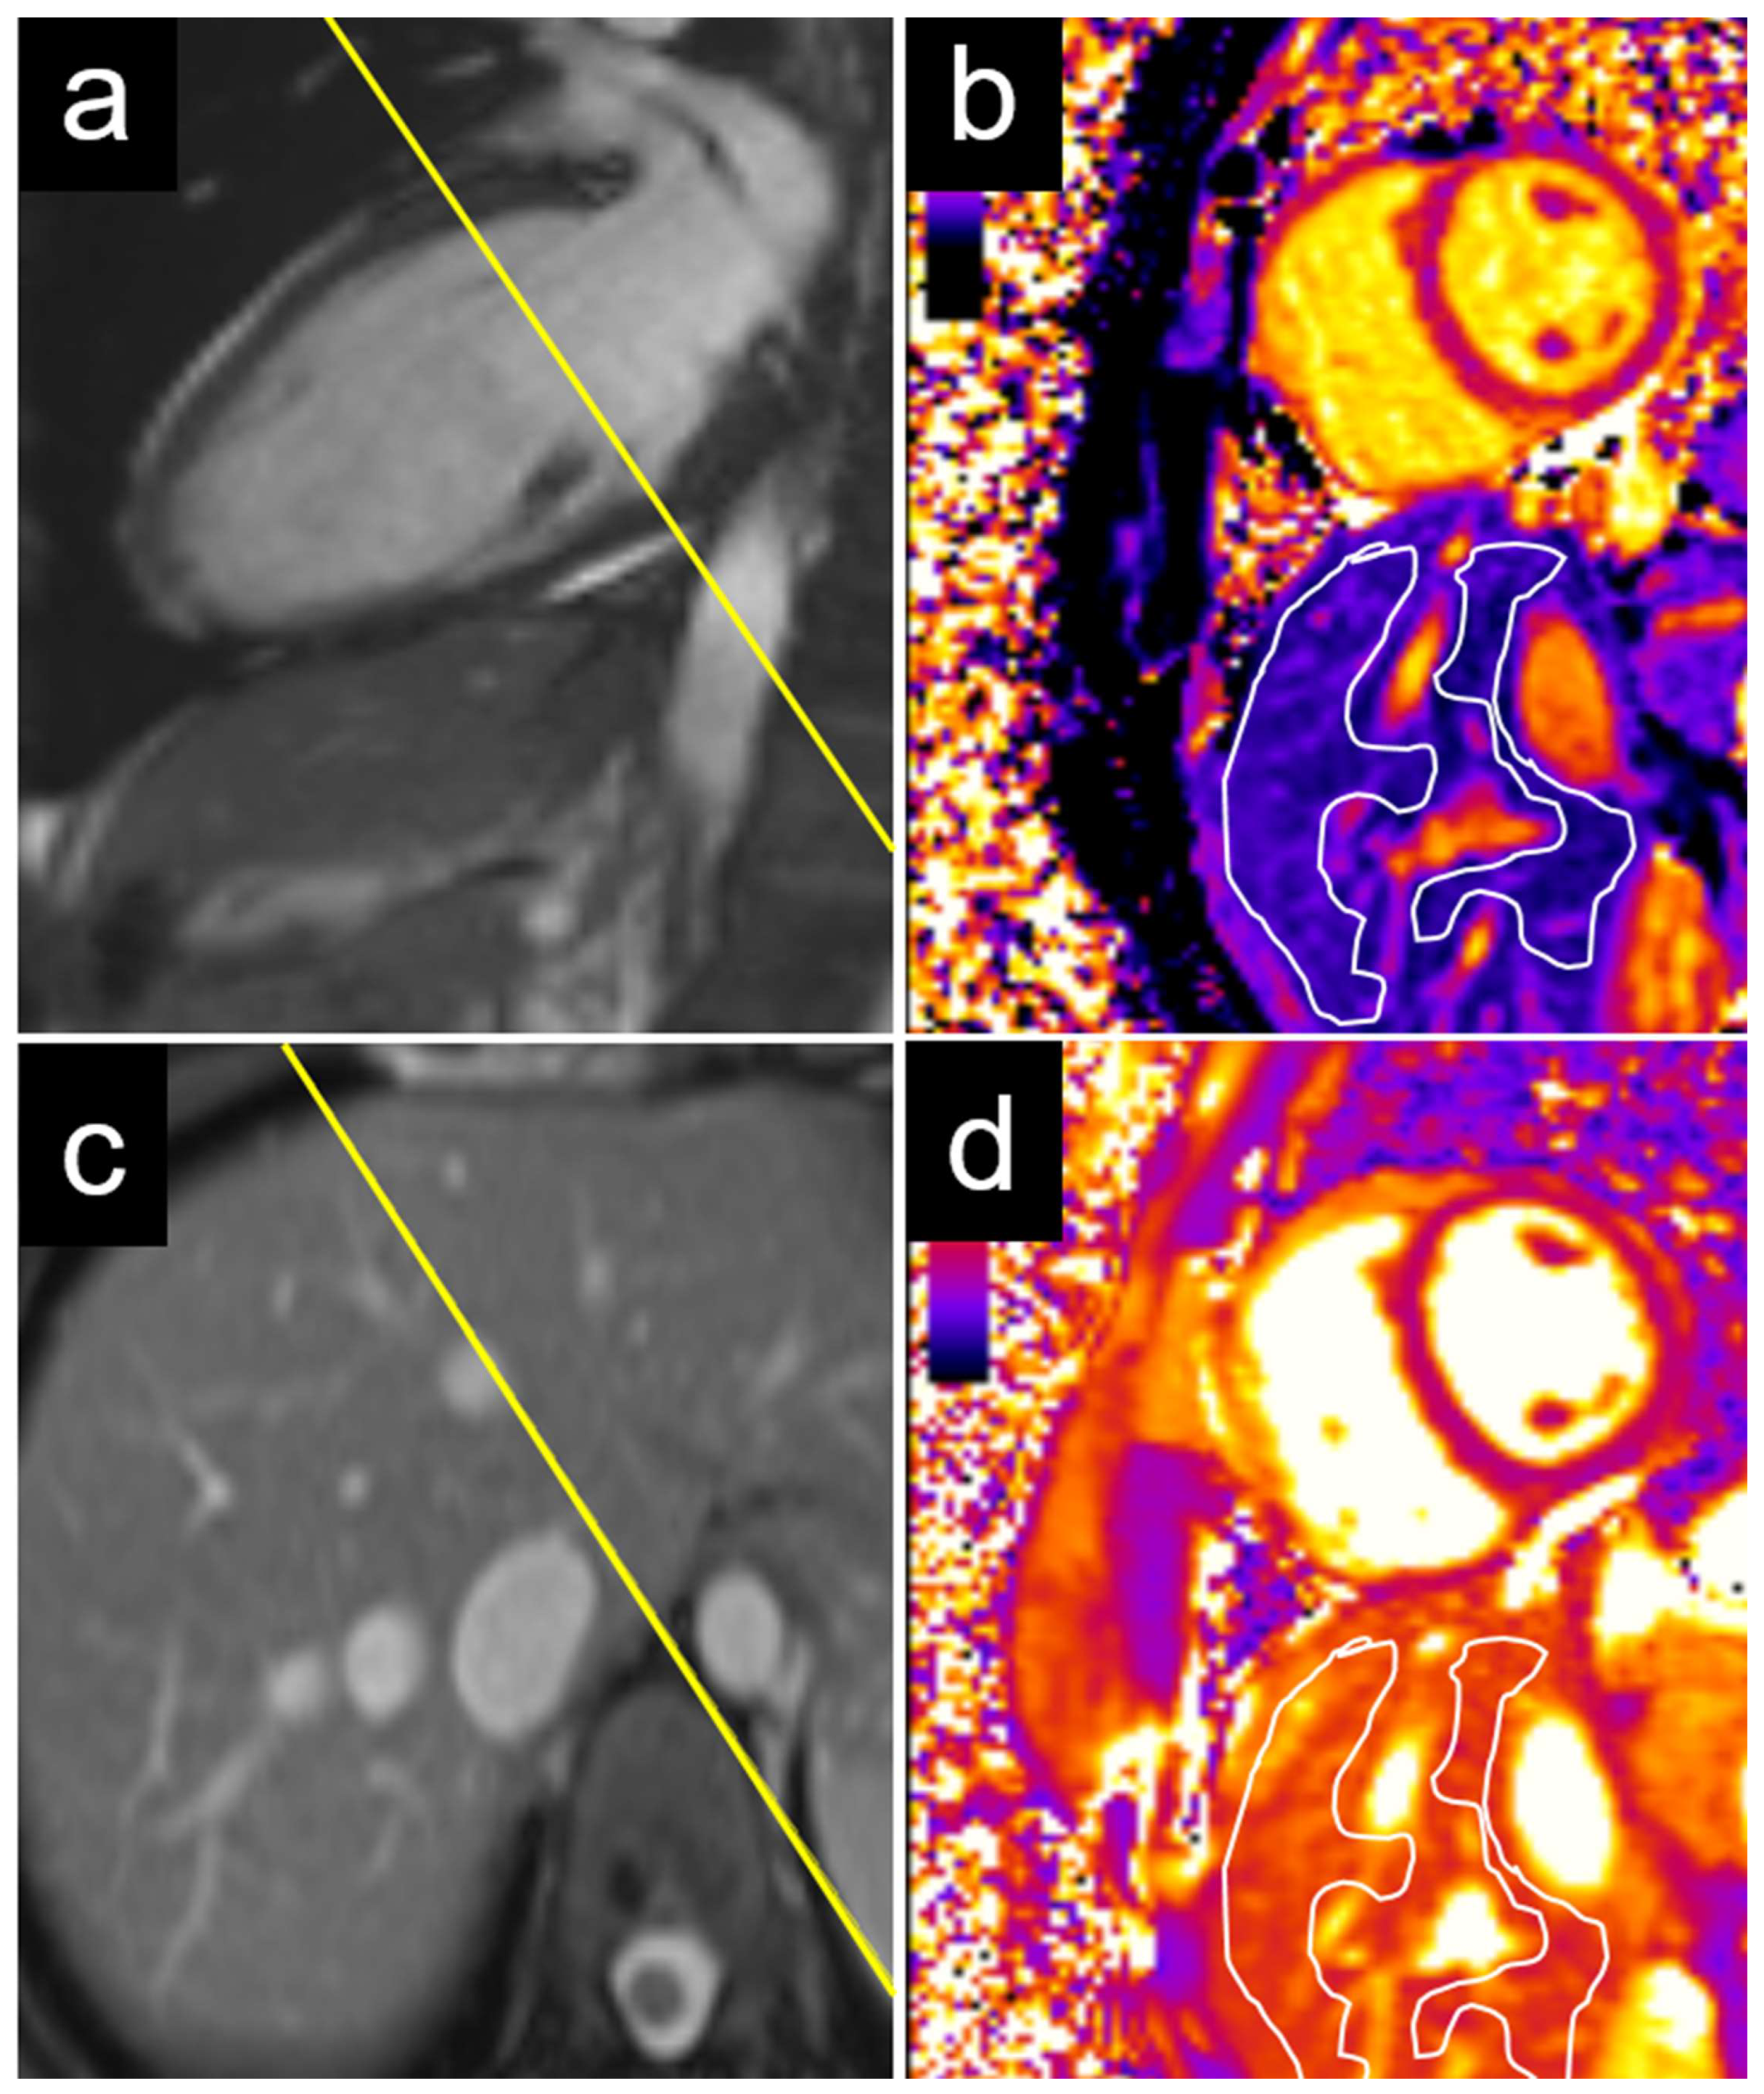

An echocardiographic evaluation revealed similar results, with significant differences in the T1 values between patients with elevated and non-elevated left ventricular filling pressures in the caudate and right liver lobes, but not in the left lobe or liver dome (Table 3). Examples of the liver T1 and T2 measurements are provided for a patient with normal NT-proBNP levels (Figure 3) and for a patient with elevated NT-proBNP levels (Figure 4).

Figure 4. Example of a 29-year-old female patient with elevated NT-proBNP. The measurements were performed on a basal short axis view (a) in the caudate and right liver lobes (c). The liver T1 was 685 ms in the right liver lobe and 543 ms in the caudate lobe (b). The liver T2 was 61 ms in the right liver lobe and 59 ms in the caudate lobe (d). NT-proBNP = N-terminal pro b-type natriuretic peptide.